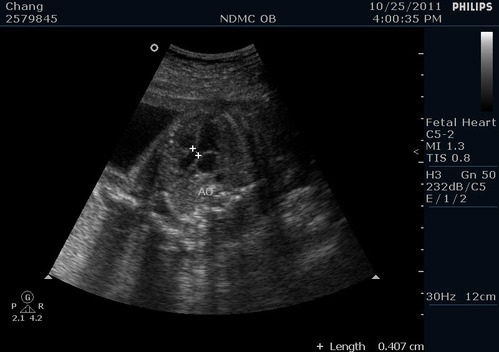

主動脈的血流狀況